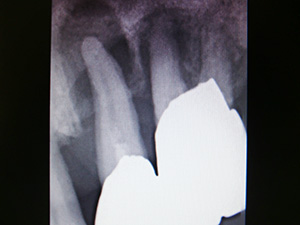

歯周病

歯周病は万病のもと!

歯周病になると、歯肉が炎症をおこし、歯がグラグラしたり、嫌な口臭がしたりします。

ところが、歯周病による影響は口の中のトラブルにとどまらず、肺炎、糖尿病、心疾患、動脈硬化、早産などの疾患につながることが、わかってきました。